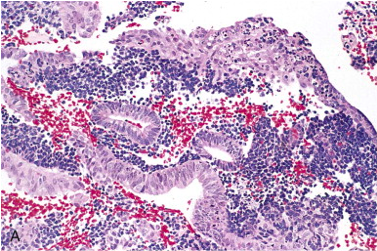

What does the endometrium look like during the menses phase of menstruation?

Tissue begins to almost ball up to be sloughed and hemorrhage can be seen

POC= product of conception (below- chorionic villi)

Look for plasma cells!!